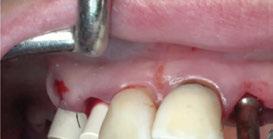

3. Fase quirúrgica final

La cirugía se realizó bajo sedación consciente y anestesia local (articaína 4% con epinefrina 40/0,01 mg/ml Ultracain®, 5 carpules en vestibular y palatino de la arcada superior). En primer lugar, se realizaron las exodoncias de los dientes remanentes 11, 21 y 24 y, a continuación, se adaptó la férula de cirugía guiada dentosoportada, insertando los implantes elegidos, en este caso en las posiciones 11 y 21 de Zimvie Tapered Screw-Vent Z3D de 3,7 por 13 mm, 14 Zimvie Tapered Screw-Vent Z3D de 3,7 por 13 mm y 16, 24 y 26 de Zimvie Tapered Screw-Vent Z3D de 4,7 por 13 mm, quedando todos ellos a un torque mayor a 30 Nm. Posteriormente, se realizaron el resto de exodoncias,

produciéndose la fractura de la tabla vestibular del 23, la cual se fijó con un tornillo de osteosíntesis, tras abrir un colgajo mucoperióstico. A continuación, se procedió al relleno de los alveolos que harán de pónticos y los gaps con GEISTLICH BIO-OSS® COLLAGEN 100 mg.

Seguidamente, se colocaron los pilares cónicos TSV-TM de Zimmer® y se atornillaron los pilares provisionales de titanio (Figuras 17-23).